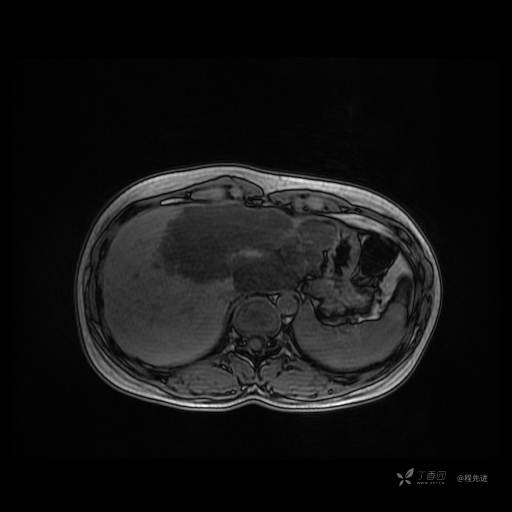

MR平扫+增强

每个序列一张图像(图像太多了,恕不一一发上来)